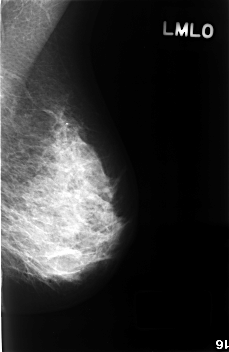

C_0393_1.LEFT_MLO

LEFT_MLO LINES 4568 PIXELS_PER_LINE 2976 BITS_PER_PIXEL 12 RESOLUTION 50 NON_OVERLAY